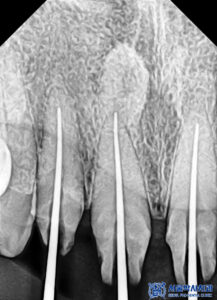

파노라마를 촬영하고

확인해 보았을 때도,

보철물이 방사선불투과성이라

치아 내부를 정밀하게

확인할 수 없었습니다.

충치를 제거하고

신경치료를 시작하였습니다.